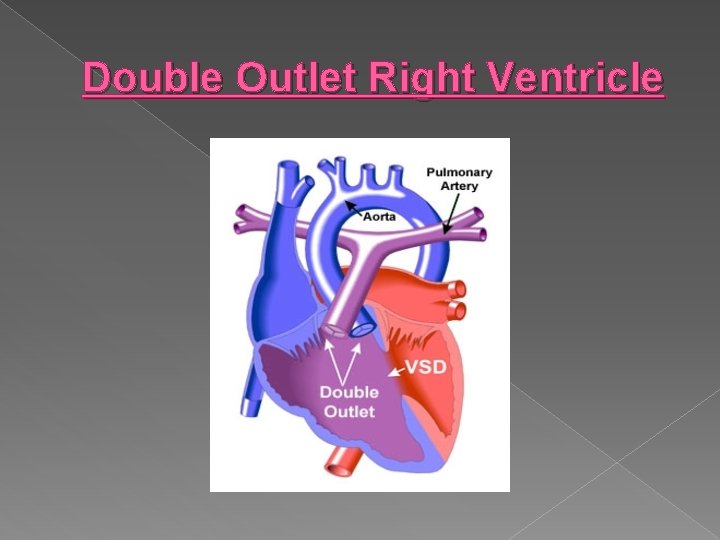

Double Outlet Right Ventricle � Both the pulmonary artery and the aorta arise from the right ventricle. This defect is associated with other cardiac defects, maternal diabetes, and maternal alcohol consumption.

Double Outlet Right Ventricle